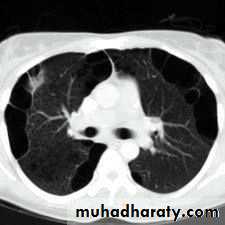

History; too shy to take of his shirt in the pool!